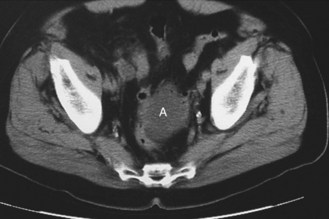

Fig. 8.13 Surgical stomas.

A, An ileostomy is usually in the right iliac fossa and is formed as a spout. B, A loop colostomy is created to defunction the distal bowel temporarily. It is usually in the transverse colon and has afferent and efferent limbs. C, A colostomy may be terminal, i.e. resected distal bowel. It is usually flush and in the left iliac fossa.